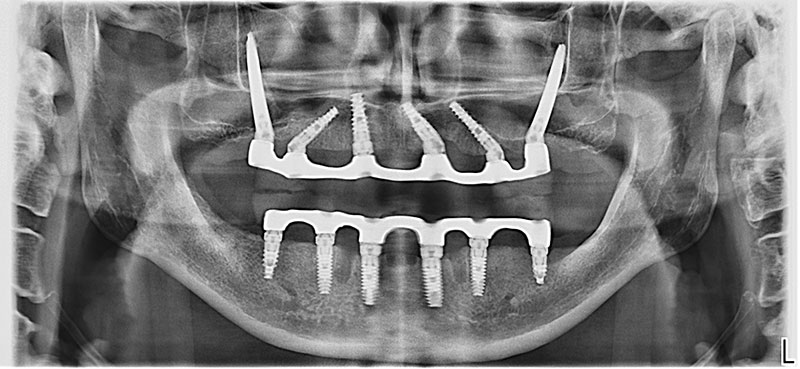

ОПТГ после операции

Комплексная Имплантация по системе All-on-6 верхней и нижней челюстей (вживление 10 классических имплантатов Noris Medical Tuff (Израиль) и 2 скуловых имплантатов Noris Medical ZYGOMATIC (Израиль) и установка армированных протезов по передовой методике протезирования All-on-6).